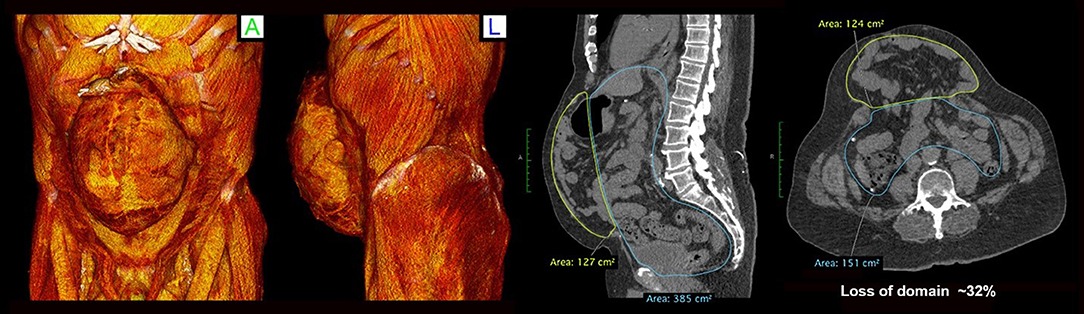

Loss of abdominal domain

Patients with complex hernias, a history of failed hernia repairs, or abdominal trauma may require abdominal wall reconstruction. Large hernias can cause abdominal deformities, discomfort, and a significant impact on quality of life. These hernias do not resolve without surgical intervention.

The Procedure